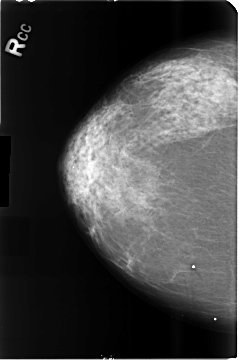

Volume: cancer_15 Case: B-3514-1

B_3514_1.RIGHT_CC

RIGHT_CC LINES 4680 PIXELS_PER_LINE 3104 BITS_PER_PIXEL 12 RESOLUTION 50 NON_OVERLAY